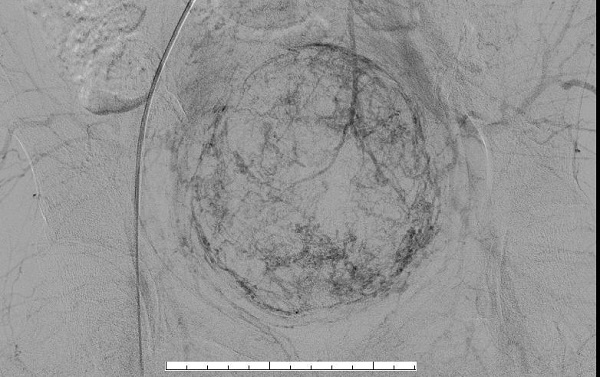

手术从股动脉进行血管穿刺,创伤小,恢复快,完整保留子宫。术中可见子宫肌瘤血供明显。

(栓塞前子宫肌瘤血管显影)